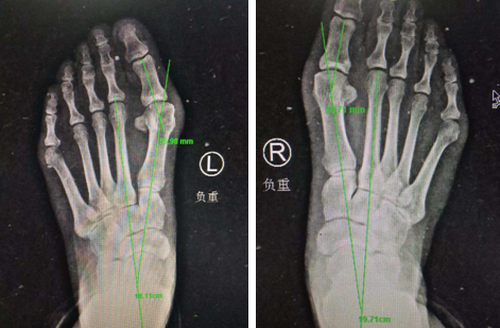

术前X线

李大姐多方打听,3月11日上午,她来到必威官方首页官网betway足踝外科专家门诊,找到了业务院长石荣剑。石院长为病人做过体检和相关影像检查后,考虑患者二次手术,恐惧开大切口,决定为患者实施微创踇外翻矫正术。

石院长介绍,我院整形美容科采用韩国进口低频超声微磨锯实施颌面整形美容手术,切口很小,4毫米微磨锯锋利、精准、自带注水降温。受到启发,足踝外科创造性地将其优点运用到踇外翻微创治疗中去:不到1厘米切口无需缝合;微创截骨自带降温会更好的保护骨骼血运,从而截骨处会更快的愈合。